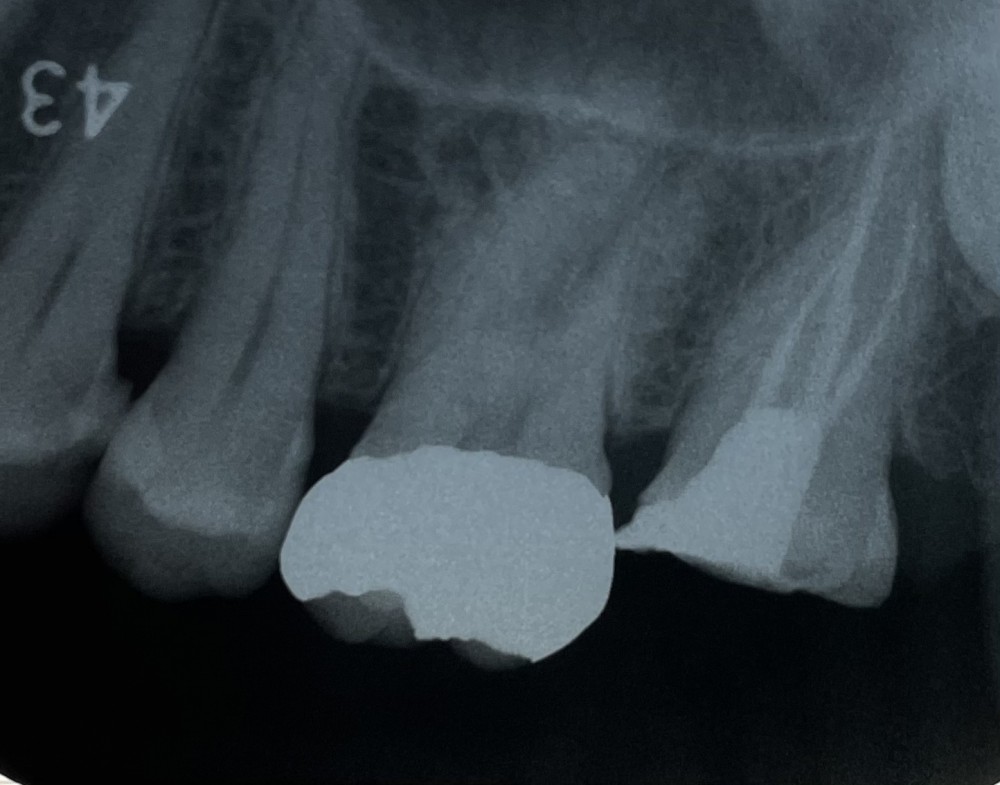

根管治療の最終段階では、ガッタパーチャーポイントにお薬を塗って、根管内に充填します。

根管充填では、試適した2根管の他に、残りの1根管もガッタパーチャーポイントを入れます。

術後のエックス線写真がこちらです。